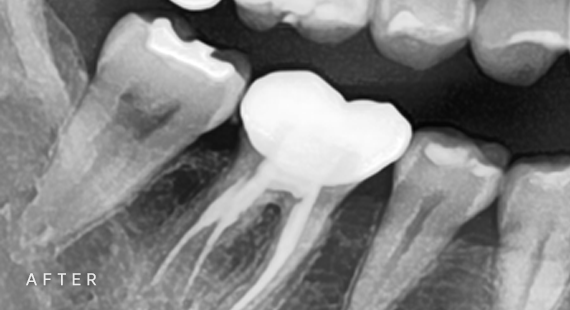

신경치료